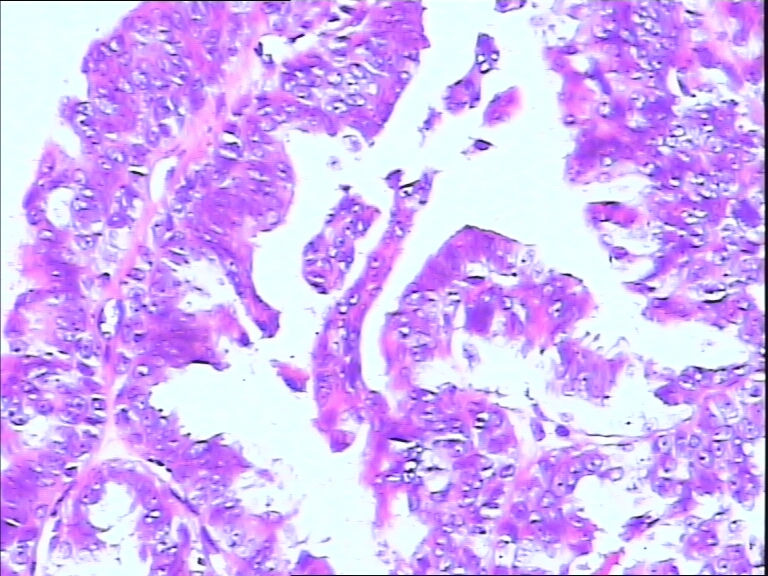

B3785左乳头包块!

42y

左乳头有3mm结节

灰白不整形组织一块:0.7*0.5*0.4

• 左乳头包块!图1

图1

标签:导管内乳头状肿瘤

诊断导管内乳头状瘤.做免疫组化肌上皮标记,排除癌变

导管内乳头状瘤

导管内乳头状瘤,导管上皮不典型增生。

乳头腺瘤(nipple duct adenoma)或称乳头的乳头状瘤

导管内乳头状瘤,局灶伴不典型增生。

导管内乳头状肿瘤.做免疫组化肌上皮标记,排除癌变。

有异性,考虑导管内乳头状癌

导管内乳头状结构,细胞无异型性,诊断导管内乳头状瘤。